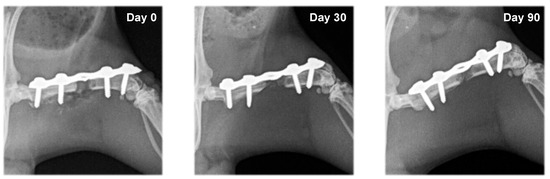

2.4. Radiography

3.2. Radiography